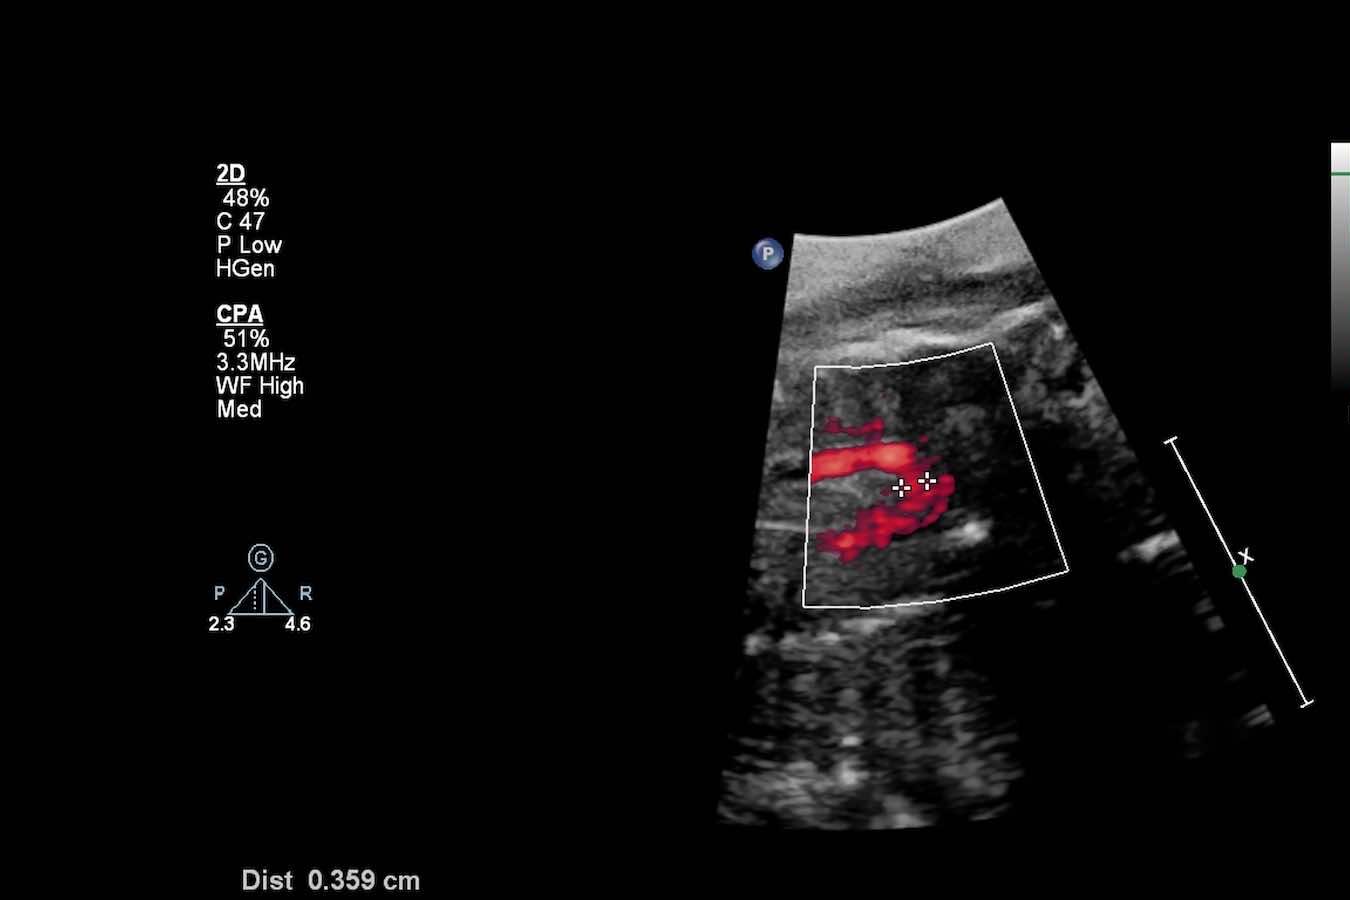

Die Kardiologie ist die Lehre vom Herzen und seinen Erkrankungen. Bei KardioPro bieten wir eine umfassende Bandbreite an diagnostischen Verfahren, um die Funktion und Struktur Ihres Herzens präzise zu beurteilen. Dazu gehören unter anderem das Ruhe- und Belastungs-EKG, der Langzeit-EKG zur Detektion von Herzrhythmusstörungen, sowie der Herzultraschall (Echokardiographie) zur Beurteilung der Herzklappen und der Pumpleistung.

Umfassende kardiologische Vorsorgeuntersuchungen basierend auf den Zusatzqualifikationen Hypertensiologie (DHL) und Lipidologie (DGFF). Wir nutzen modernste Ultraschall- und EKG-Techniken zur frühzeitigen Erkennung komplexer kardiovaskulärer Risikofaktoren und Gefäßveränderungen.